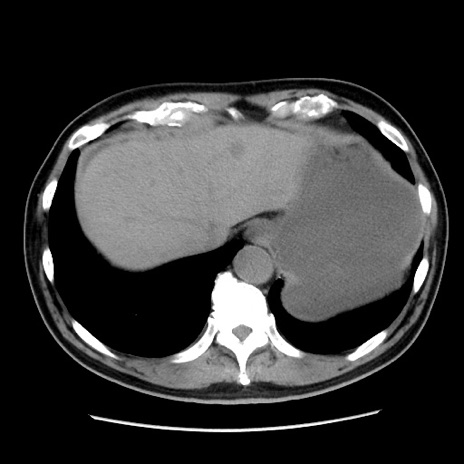

症例16(横断像)

【症例】 70歳代男性

【主訴】 腹痛、嘔吐

【現病歴】 約1ヶ月前より間欠的に腹痛と嘔吐あり、当院消化器内科を受診したところCTで多発する肝臓のLDAを指摘され、精査中であった。以降は消化器症状は安定していたが、2日前より嘔気と腹痛があり、同日より排便・排ガスが消失した。改善認めず、 本日、救急外来を受診した。

【既往歴】 大腸ポリープ切除後。

【身体所見】意識清明・会話良好、BT 36.3℃、BP 127/80mmHg、 P 80bpm、腹部:膨満あり、平坦・軟、上腹部正中および下腹部正中に圧痛あり、反跳痛なし、筋性防御なし。

【データ】WBC 7200、CRP 0.77